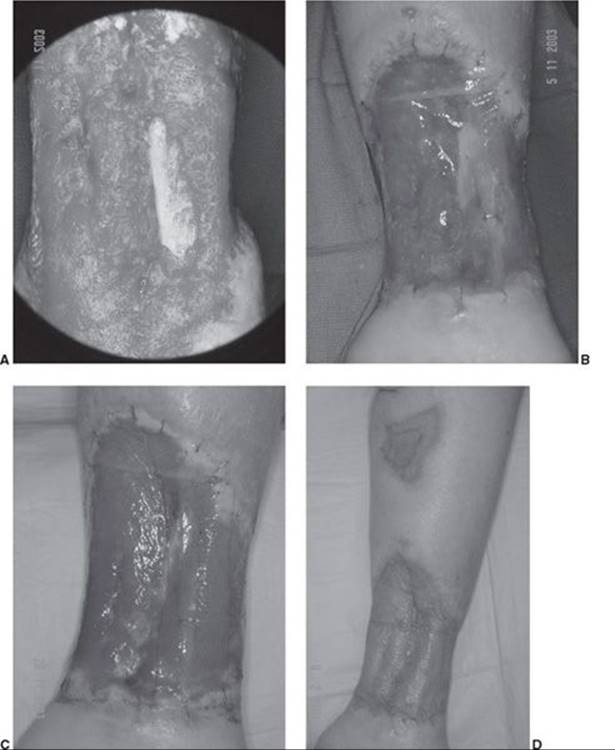

FIGURE 95.11. Ankle ulcer. A. This large ulcer above the medial ankle was debrided to clean bleeding tissue and tibia. B, C. The wound was covered with a dermal regeneration template and NPWT for 10 days. D. The silicone sheet was removed off the now vascularized dermal template and a thin autograft was applied.